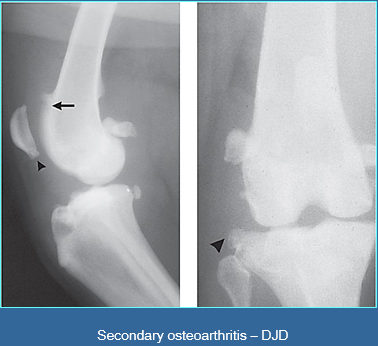

What are the arrows pointing to?

Osteophytes